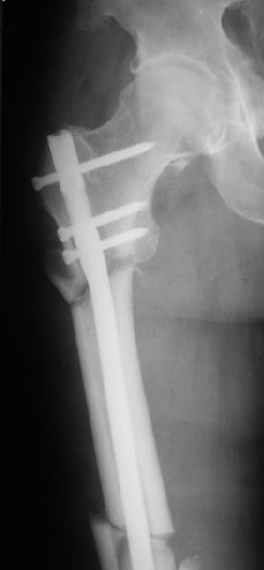

Картинка красивая, но на мой взгляд, не совсем оптимальная: Слишком медиально введён стержень - риск аваскулярного некроза головки бедра.

вариант межфрагментарного шинирования - зона достаточно простительная т.е. чрезвертельные переломы потенциально хорошо срастаются при любом

расположении сопредельных отломков- хорошая локальная васкуляризация. В приведённом случае я бы предпочёл принцип межфрагментарной компрессии (рекон/гамма нэйл 130- 135) принципу шинирования перелома.

Поясни, пожалуйста, почему решил шинировать косой чрезвертельный перелом?

Женя, эта картинка показывает не оптимальное лечение вертельных переломов в моем представлении, а особенности дизайна упомяутого фиксатора.

В частности, его возможности при фиксации переломов проксимального отдела бедра - в сравнении с другими, имеюшими лишь по одному статическому и динамическому отверстию и с кондуктором для введения 2 винтов.

Это было года 2,5 назад, мы тогда еще уточняли возможности шинирования с угловой стабильностью гвоздем с поперечным расположением винтов при переломах проксимального отдела бедра. Пациенту не пришлось приобретать намного более дорогой рекон или проксимальный гвоздь. В приложении еще несколько примеров применения того гвоздя при высоких переломах бедра, в том числе с более латеральной точкой входа. Гвоздь изгибаем для этого.